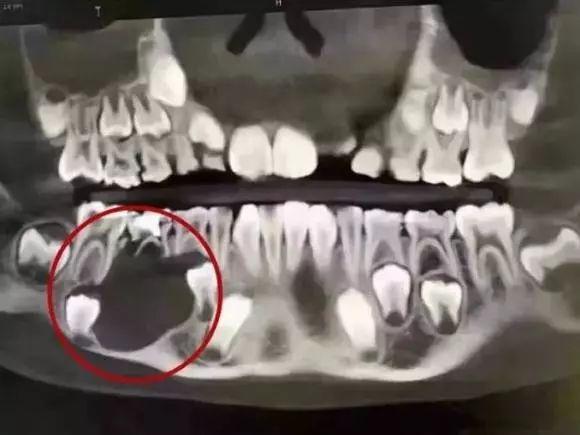

无独有偶,我们再看另一个9岁孩童的案例:

一位9岁的孩子,因父母没有重视乳牙护理和龋齿调节,那颗乳牙下面的颌骨大面积吸收!当然,囊肿造成的但乳牙根尖周炎,也可能是这种吸收的可能原因之一(由于没有详细资料和医生的诊断)。

图像上黑色的阴影部分是下颌骨大面积破坏后的成像,太可怕了!